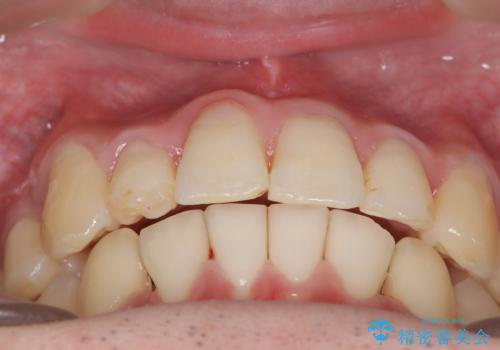

前歯のガタガタを治したい。

- 凸凹を治したいと来院された患者様です。

インビザラインにて、遠心移動を行いながら綺麗に配列することができました。